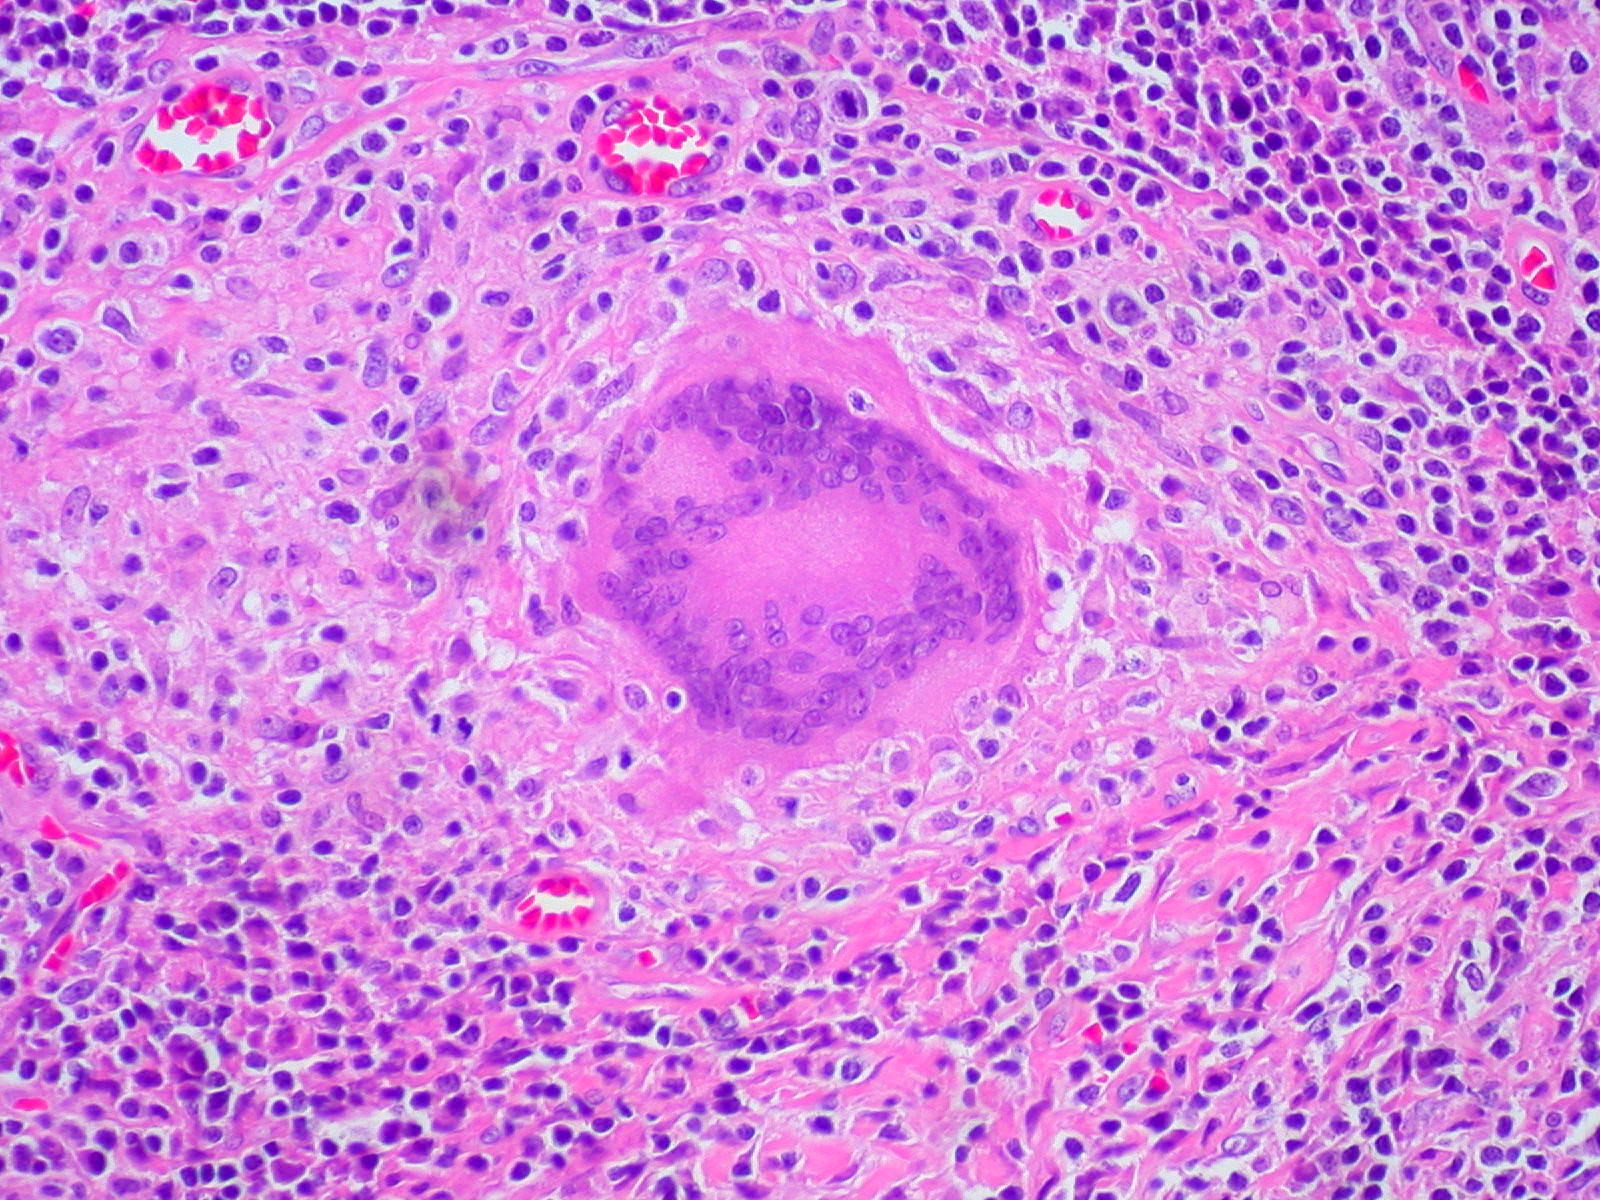

PA:Histologisch is er een granulomateus

lymfohistiocytair ontstekingsinfiltraat dat in een uitgezette dermale papil

ligt. De overliggende epidermis is dun, en de retelijsten aan de zijkanten van

het infiltraat reiken diep waardoor het er uit ziet als een klauw die een bal

vasthoudt (ball-and-claw). Het infiltraat is nodulair en bestaat uit lymfocyten

en (deels epitheloide) histiocyten, gewoonlijk met enkele reuscellen van het

Langhans type. Er zijn enige vacuolaire veranderingen in het grensvlak. Er is

pigmentincontinentie. De epidermis toont hierboven geringe compacte hyperkeratose,

soms parakeratose. Het infiltraat wordt omsloten door verlengde retelijsten

die het infiltraat als het waren 'omarmen' (hugging).